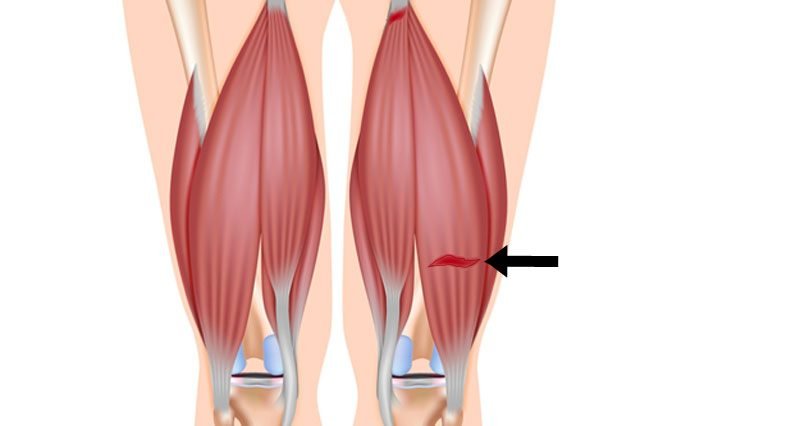

Old: Hamstring Strains

Did you know that every person has 3 hamstring muscles that work to help move the leg? But what happens when one of them gets injured? What is a hamstring strain? Read on to find out.